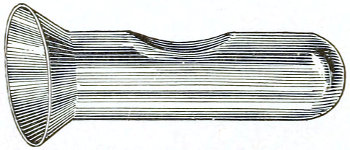

The Vaginal Speculum.—The speculum is an instrument through which a visual examination is made of the vagina, the external os uteri, and the vaginal cervix. A 29 great number of specula have been invented. At the present day the best two instruments of this class are the bivalve speculum, such as Goodell’s (Fig. 6), and the duck-bill speculum (Fig. 7), or perineal retractor, invented by Sims.

Fig. 6.—Goodell’s speculum.

Fig. 7.—Sims’ speculum.

Fig. 8.—Sims’ depressor for the anterior vaginal wall.

The bivalve speculum is introduced with the woman upon her back, in the dorso-sacral position already described. The vulva and the vagina should be cleaned. The speculum should be warmed by placing it in hot water, and should then be lubricated with the soap solution or with vaseline. It should be introduced with the blades closed and the plane of the blades lying not exactly 30 in the median sagittal plane of the body, but inclined at a small acute angle to this plane, one edge of the speculum being directed toward either vaginal sulcus. The instrument is passed into the vagina toward the position in which, by a previous digital examination, the vaginal cervix had been found to lie. The instrument is then turned with the handles toward either thigh, so that the blades become parallel to the anterior and posterior vaginal walls, in order that, when separated, they will open the vaginal slit. The handles are brought together and the blades opened. When the vaginal cervix comes well into view the blades are fixed in place by the screws (Fig. 9).

Fig. 9.—Goodell’s speculum in position.

In some cases, where the cervix points well forward or well backward, it may be readily brought into view through the speculum by catching it with a tenaculum.

By means of the bivalve speculum we are able to make a partial inspection of the vaginal walls, an imperfect inspection of the vaginal vault, and a good inspection of the vaginal cervix and the external os. Applications 31 can be made to the cervix, but none of the minor operations of gynecology can be performed through this speculum.

The Sims speculum enables us to make the most thorough inspection of the vagina, the vaginal vault, and the vaginal cervix. The Sims speculum is merely a hook or retractor for the perineum, and may be introduced with the woman in the dorsal position, the Sims position, or the genu-pectoral position. If the Sims speculum is introduced in the dorso-sacral position, it is necessary to hold forward the anterior vaginal wall in order to obtain a view of the cervix.